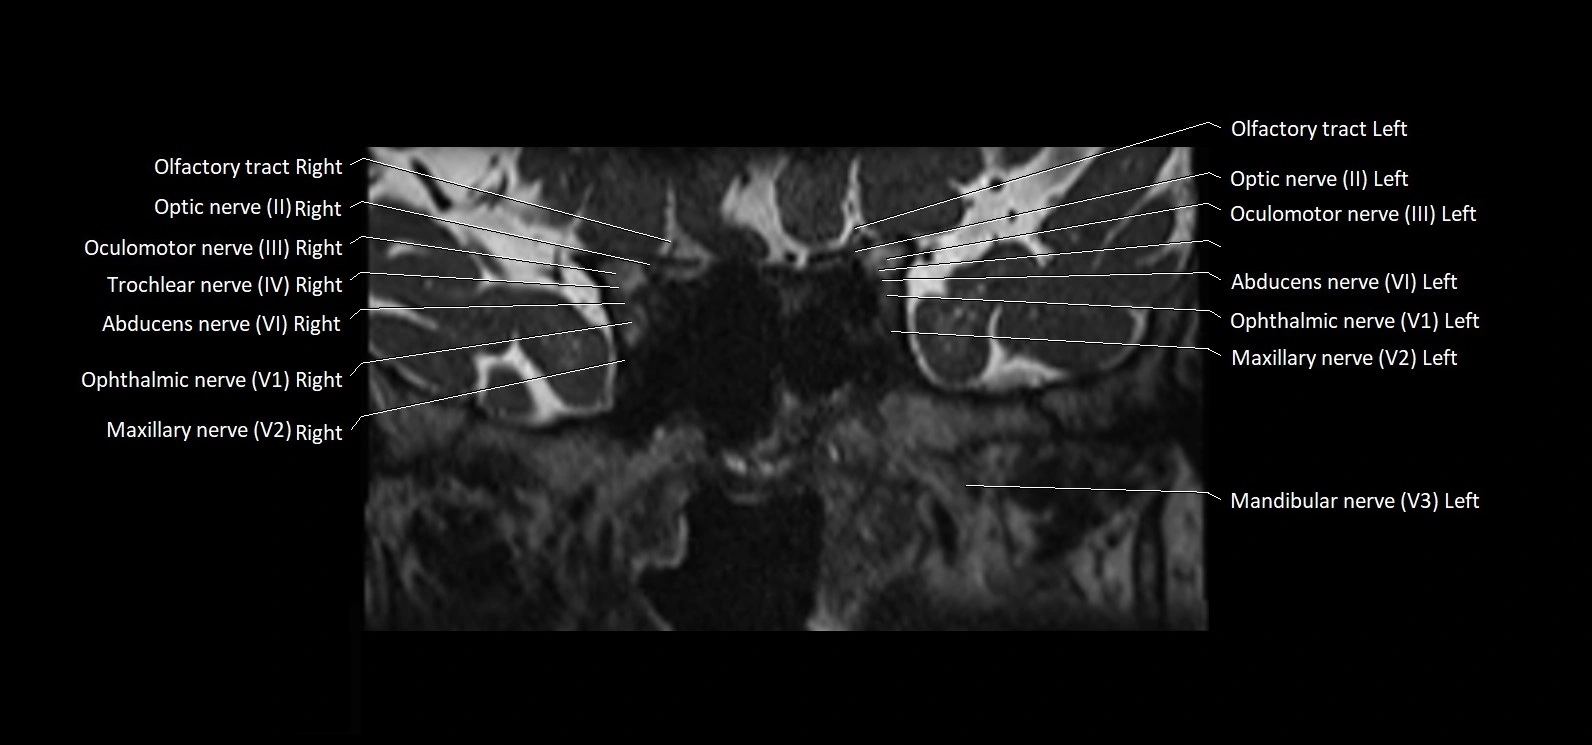

MRI Appearance

• The abducens nerve is a small, thin, linear structure

• Best visualized on high-resolution T2-weighted 3D MRI sequences (e.g., FIESTA or CISS)

• Seen as a hypointense (dark) line running from the brainstem at the pontomedullary junction, traversing the prepontine cistern, and entering Dorello’s canal under the petrosphenoidal ligament, then into the cavernous sinus, and finally the orbit

• May be challenging to visualize in standard MRI due to its small size

• Pathology may be inferred by absence, displacement, or enhancement of the nerve

MRI images

image